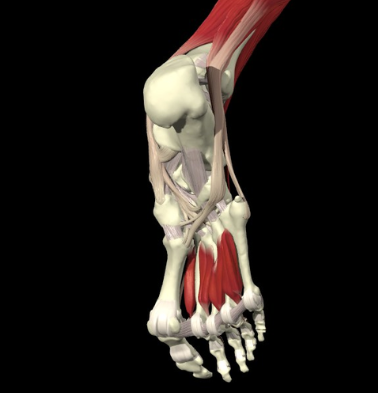

2. 단비골근(peroneus brevis, fibularis brevis)

It arises from the lower two-thirds of the lateral surface of the body of the fibula; medial to the fibularis longus; and from the intermuscular septa separating it from the adjacent muscles on the front and back of the leg.

The fibers pass vertically downward, and end in a tendon which runs behind the lateral malleolus along with but in front of that of the preceding muscle, the two tendons being enclosed in the same compartment, and lubricated by a common mucous sheath.

It then runs forward on the lateral side of the calcaneus, above the trochlear process and the tendon of the Peronæus longus, and is inserted into the tuberosity at the base of the fifth metatarsal bone, on its lateral side.

The muscle assists in weak plantarflexion and eversion of the foot.